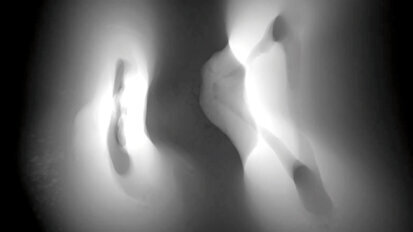

Způsobuje kojení zubní kaz?

Út. 28. července 2020